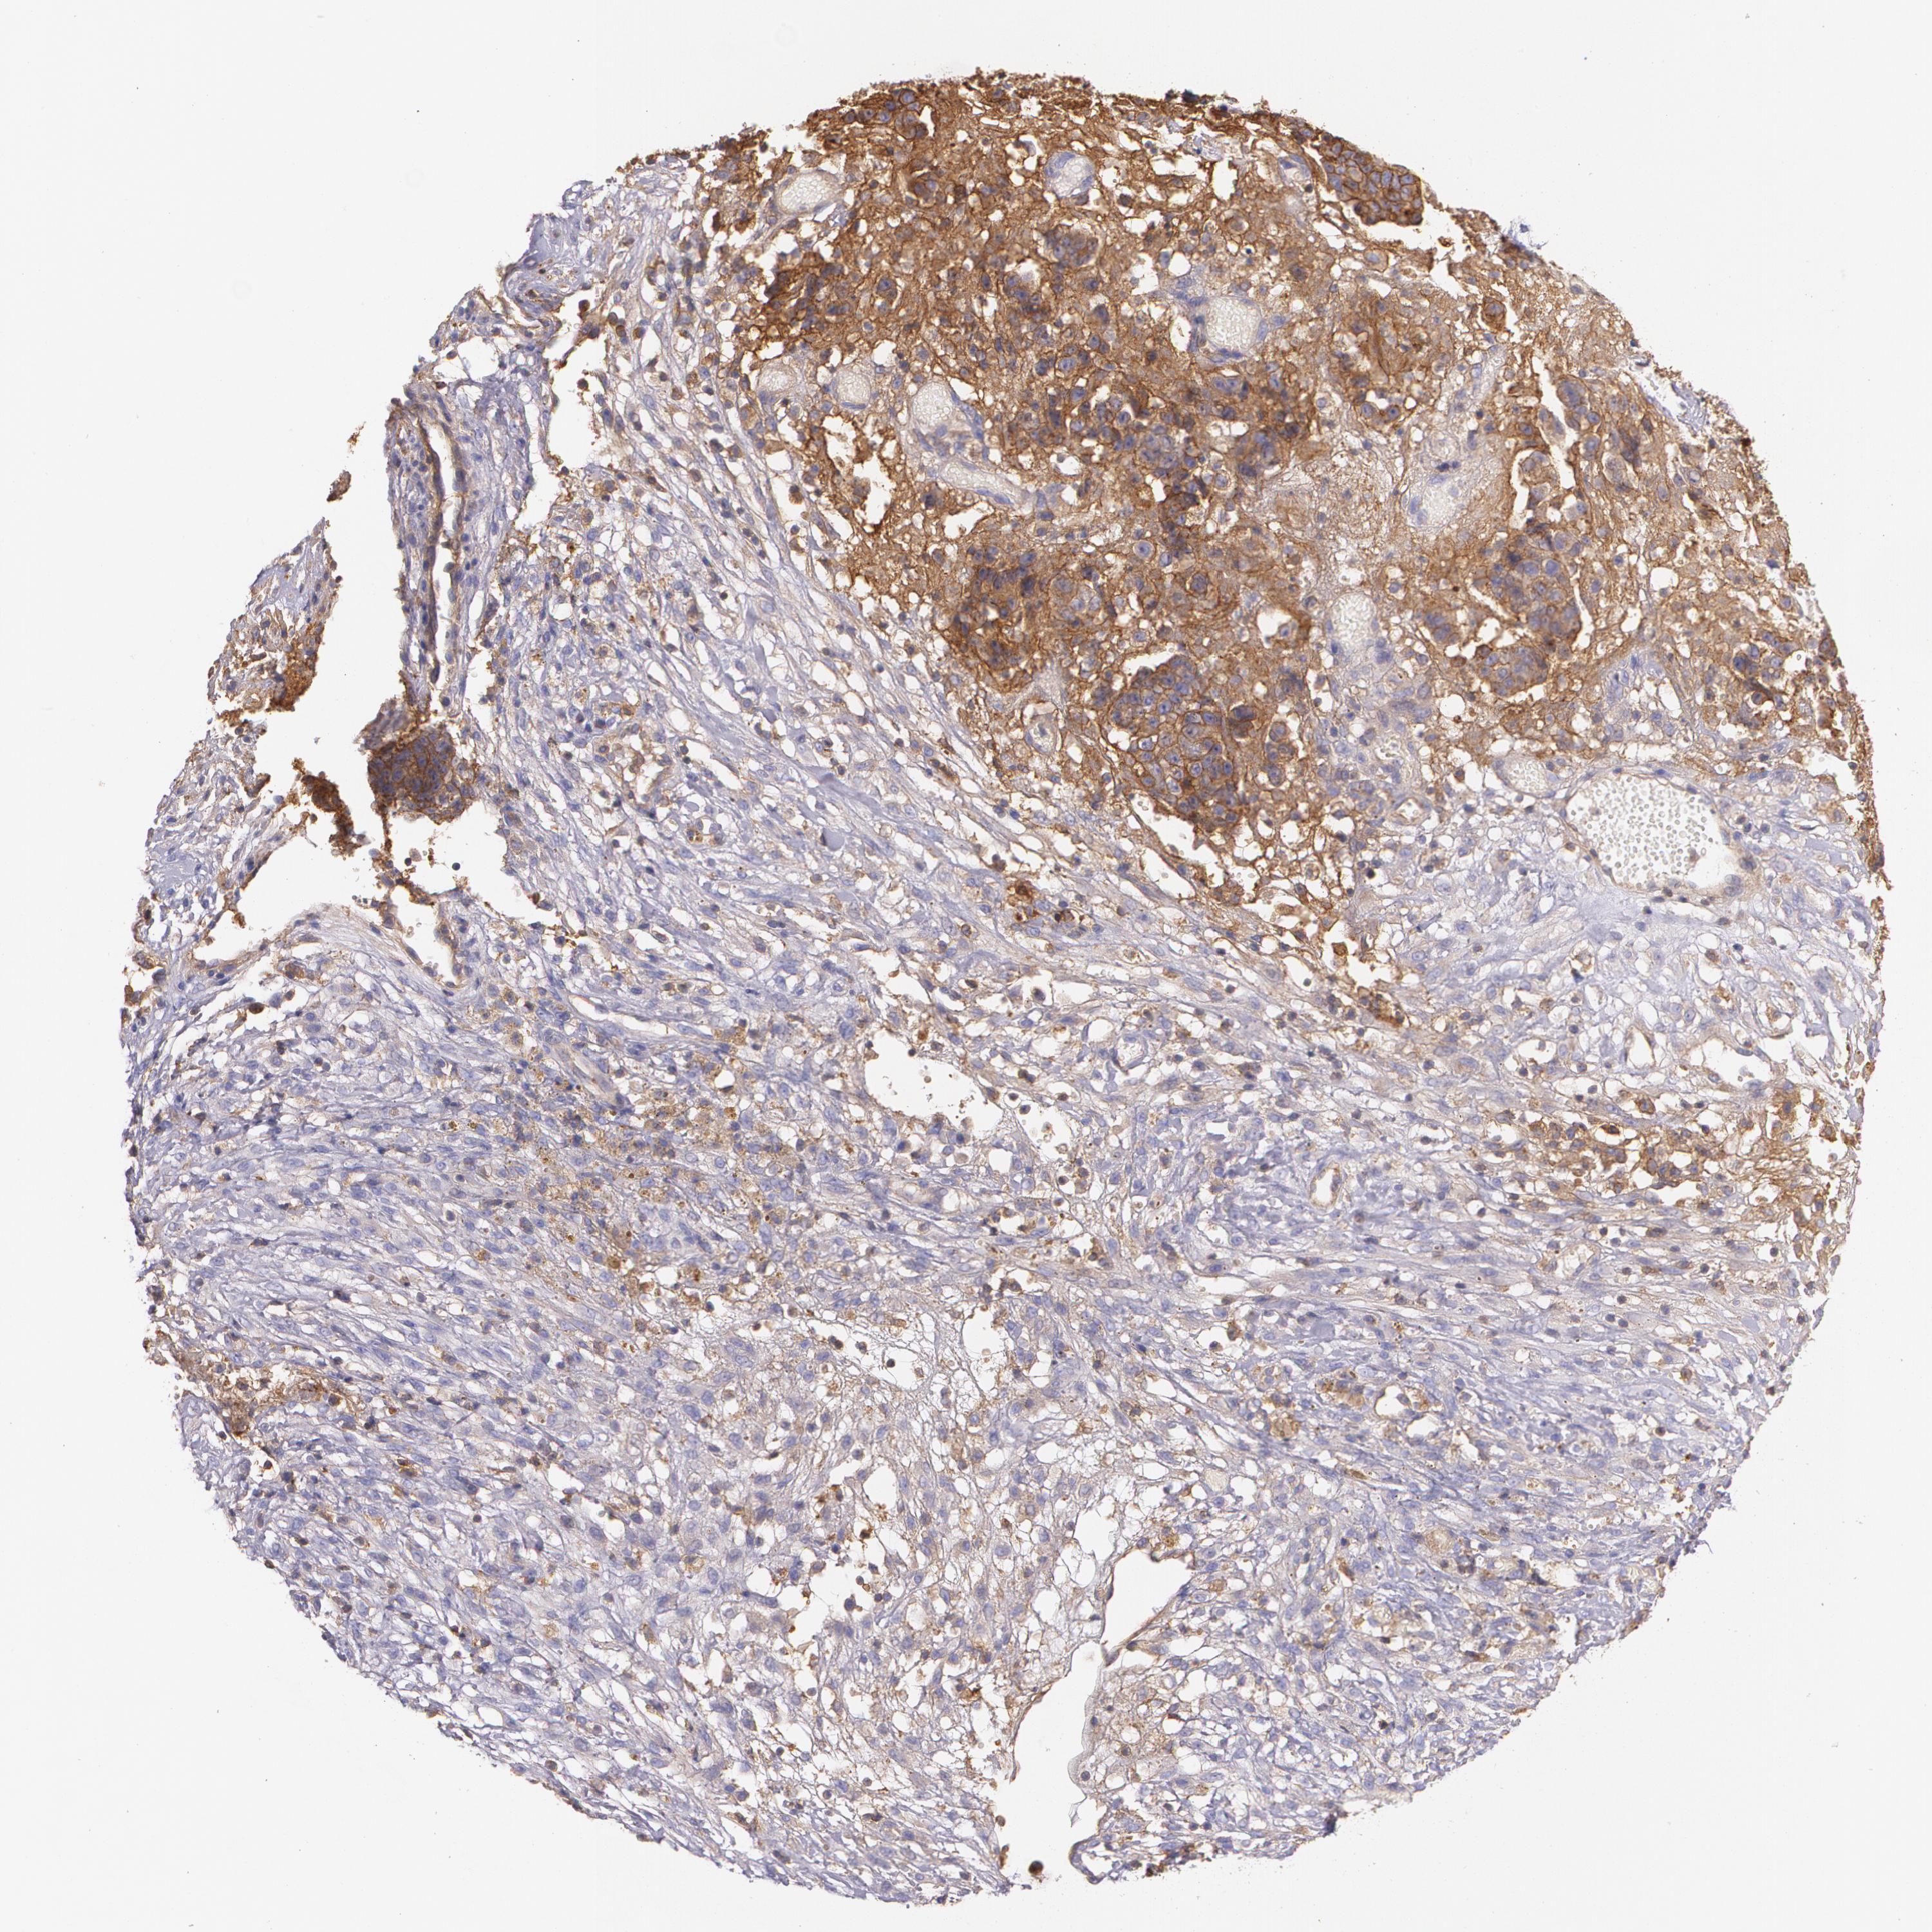

OVARIAN CANCER - Protein expressioni

A mouse-over function shows sample information and annotation data. Click on an image to view it in a full screen mode. Samples can be filtered based on level of antibody staining by selecting one or several of the following categories: high, medium, low and not detected. The assay and annotation is described here.

Note that samples used for immunohistochemistry by the Human Protein Atlas do not correspond to samples in the TCGA dataset.

Antibody stainingi

Antibody staining in the annotated cell types in the current human tissue is reported as not detected, low, medium, or high, based on conventional immunohistochemistry profiling in selected tissues. This score is based on the combination of the staining intensity and fraction of stained cells.

Each image is clickable and will lead to virtual microscopy that enables deeper exploration of all samples and also displays staining intensity scores, fraction scores and subcellular localization as well as patient and tissue information for each sample.

Antibody HPA006361

Antibody CAB002572

Staining

High

Medium

Low

Not detected

Intensity

Strong

Moderate

Weak

Negative

Quantity

>75%

75%-25%

<25%

None

Location

Nuclear

Cytoplasmic/membranous

Cytoplasmic/membranous,nuclear

Cystadenocarcinoma, serous, NOS

Carcinoma, endometroid

Carcinoma, NOS

Cystadenocarcinoma, mucinous, NOS